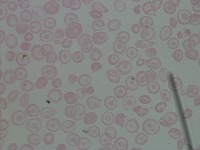

Medical Diagnosis and Research: The "New-Chula" model could be used in medical laboratories and hospitals to automatically identify and classify different cell types in blood samples. This could assist in diagnosing various blood disorders or diseases such as anemia or leukemia, thereby speeding up analysis and treatment processes.

Education and Training: The model could serve as an educational tool for medical students or professionals in training. By using this model, they could learn to identify various types of cells more quickly and accurately, enhancing their understanding of hematology.

Pharmaceutical Trials: During drug testing and development, pharmaceutical companies may use this model to analyze the impact of drugs on different cell types in order to assess effectiveness or side effects.

Public Health Monitoring: Governments and public health organizations could use it to monitor the health condition of the general population, potentially detecting the early stages of an outbreak or epidemic.

Biotechnology Industry: Biotech firms or research labs may use this model for particular research projects involving genetic modification or cellular biology studies where identification and classification of different cell types is necessary.